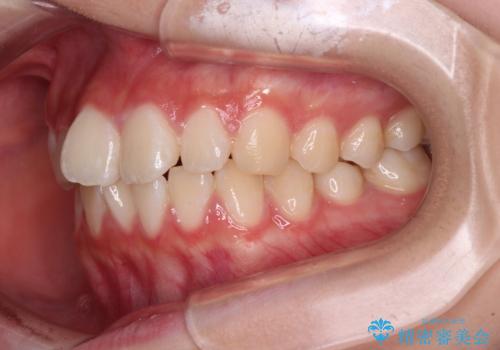

- 上下前歯のねじれを気にして来院された患者様です。

ワイヤー矯正でもマウスピース矯正でも対応可能でしたが、マウスピース矯正の自己管理が面倒であること、上顎前歯の捻転が著しいことから、ワイヤー矯正での治療を希望されました。